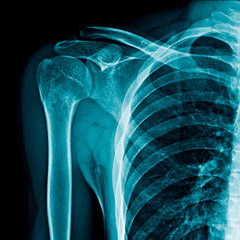

肩こりで評価すべき部位は手部、前腕、上腕。頸部、肩甲骨、内蔵まで多岐にわたります。